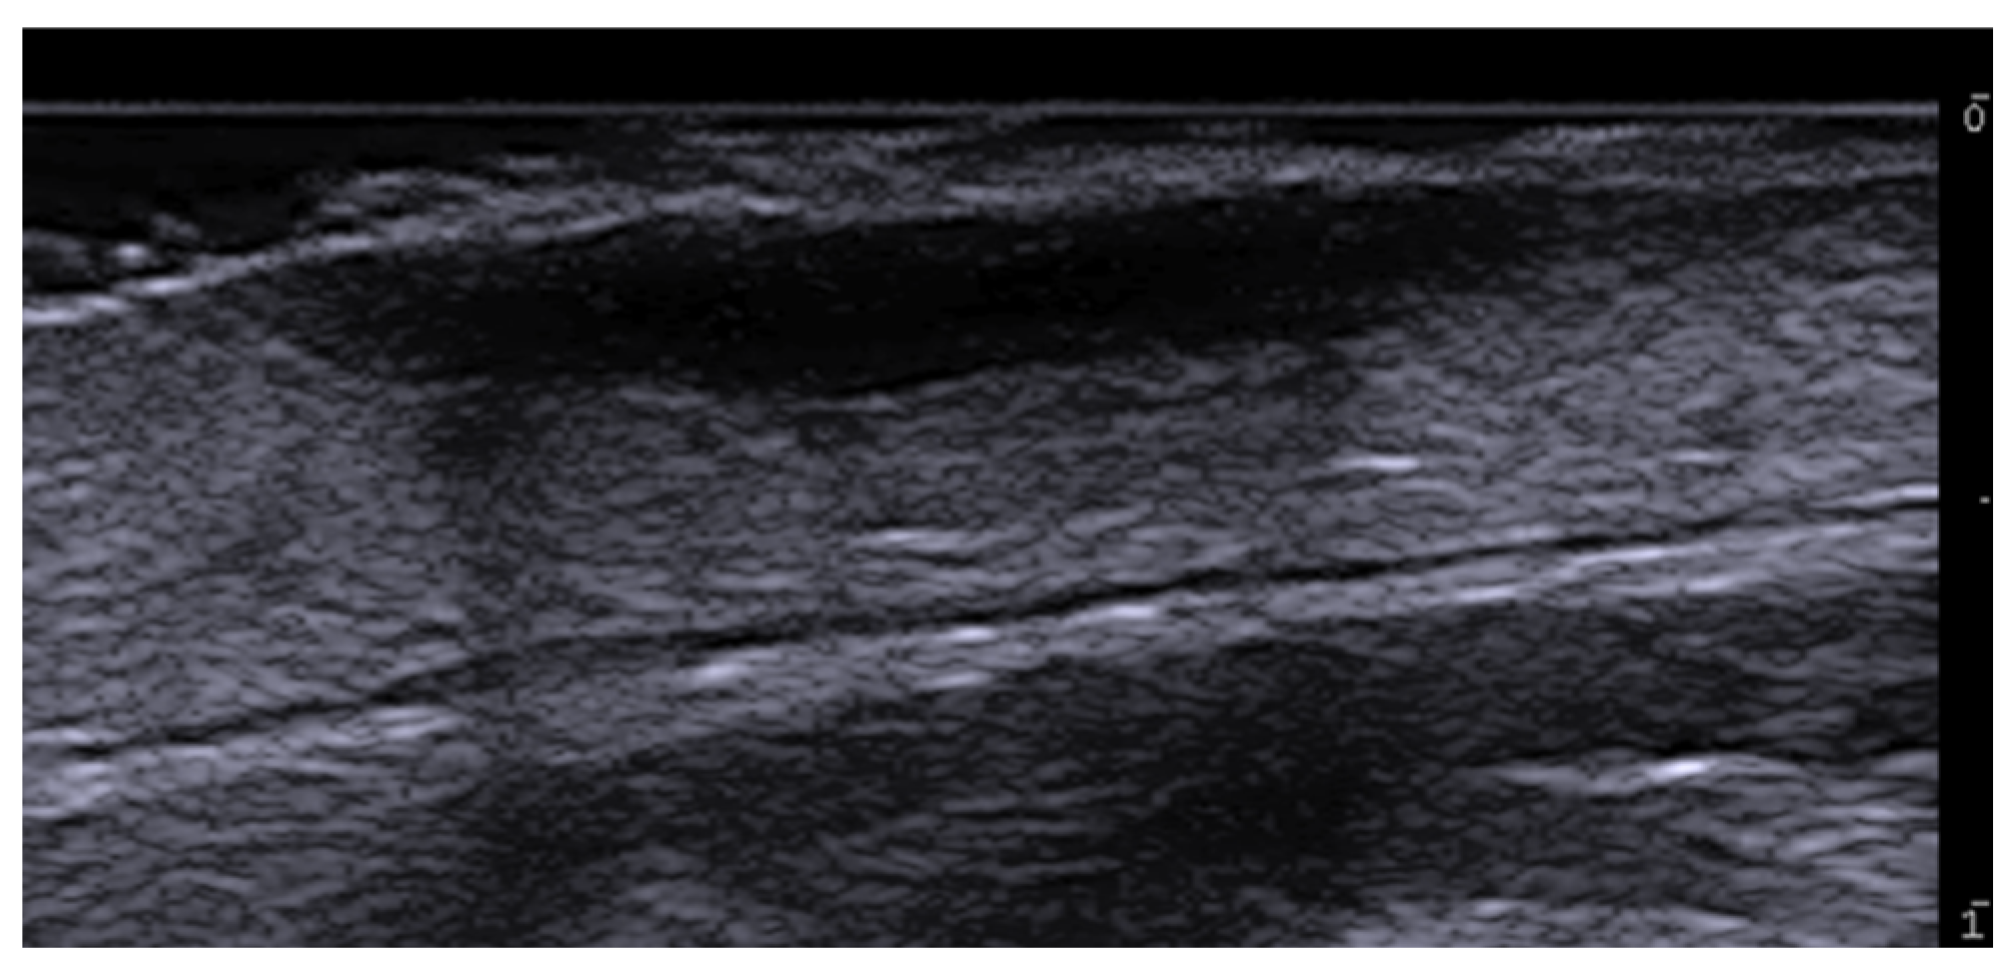

- Gonzalez, C.; Wortsman, X. How to Start on Dermatologic Ultrasound: Basic Anatomical Concepts, Guidelines, Technical Considerations, and Best Tips. Semin. Ultrasound CT MRI 2024, 45, 180–191. [Google Scholar] [CrossRef] [PubMed]